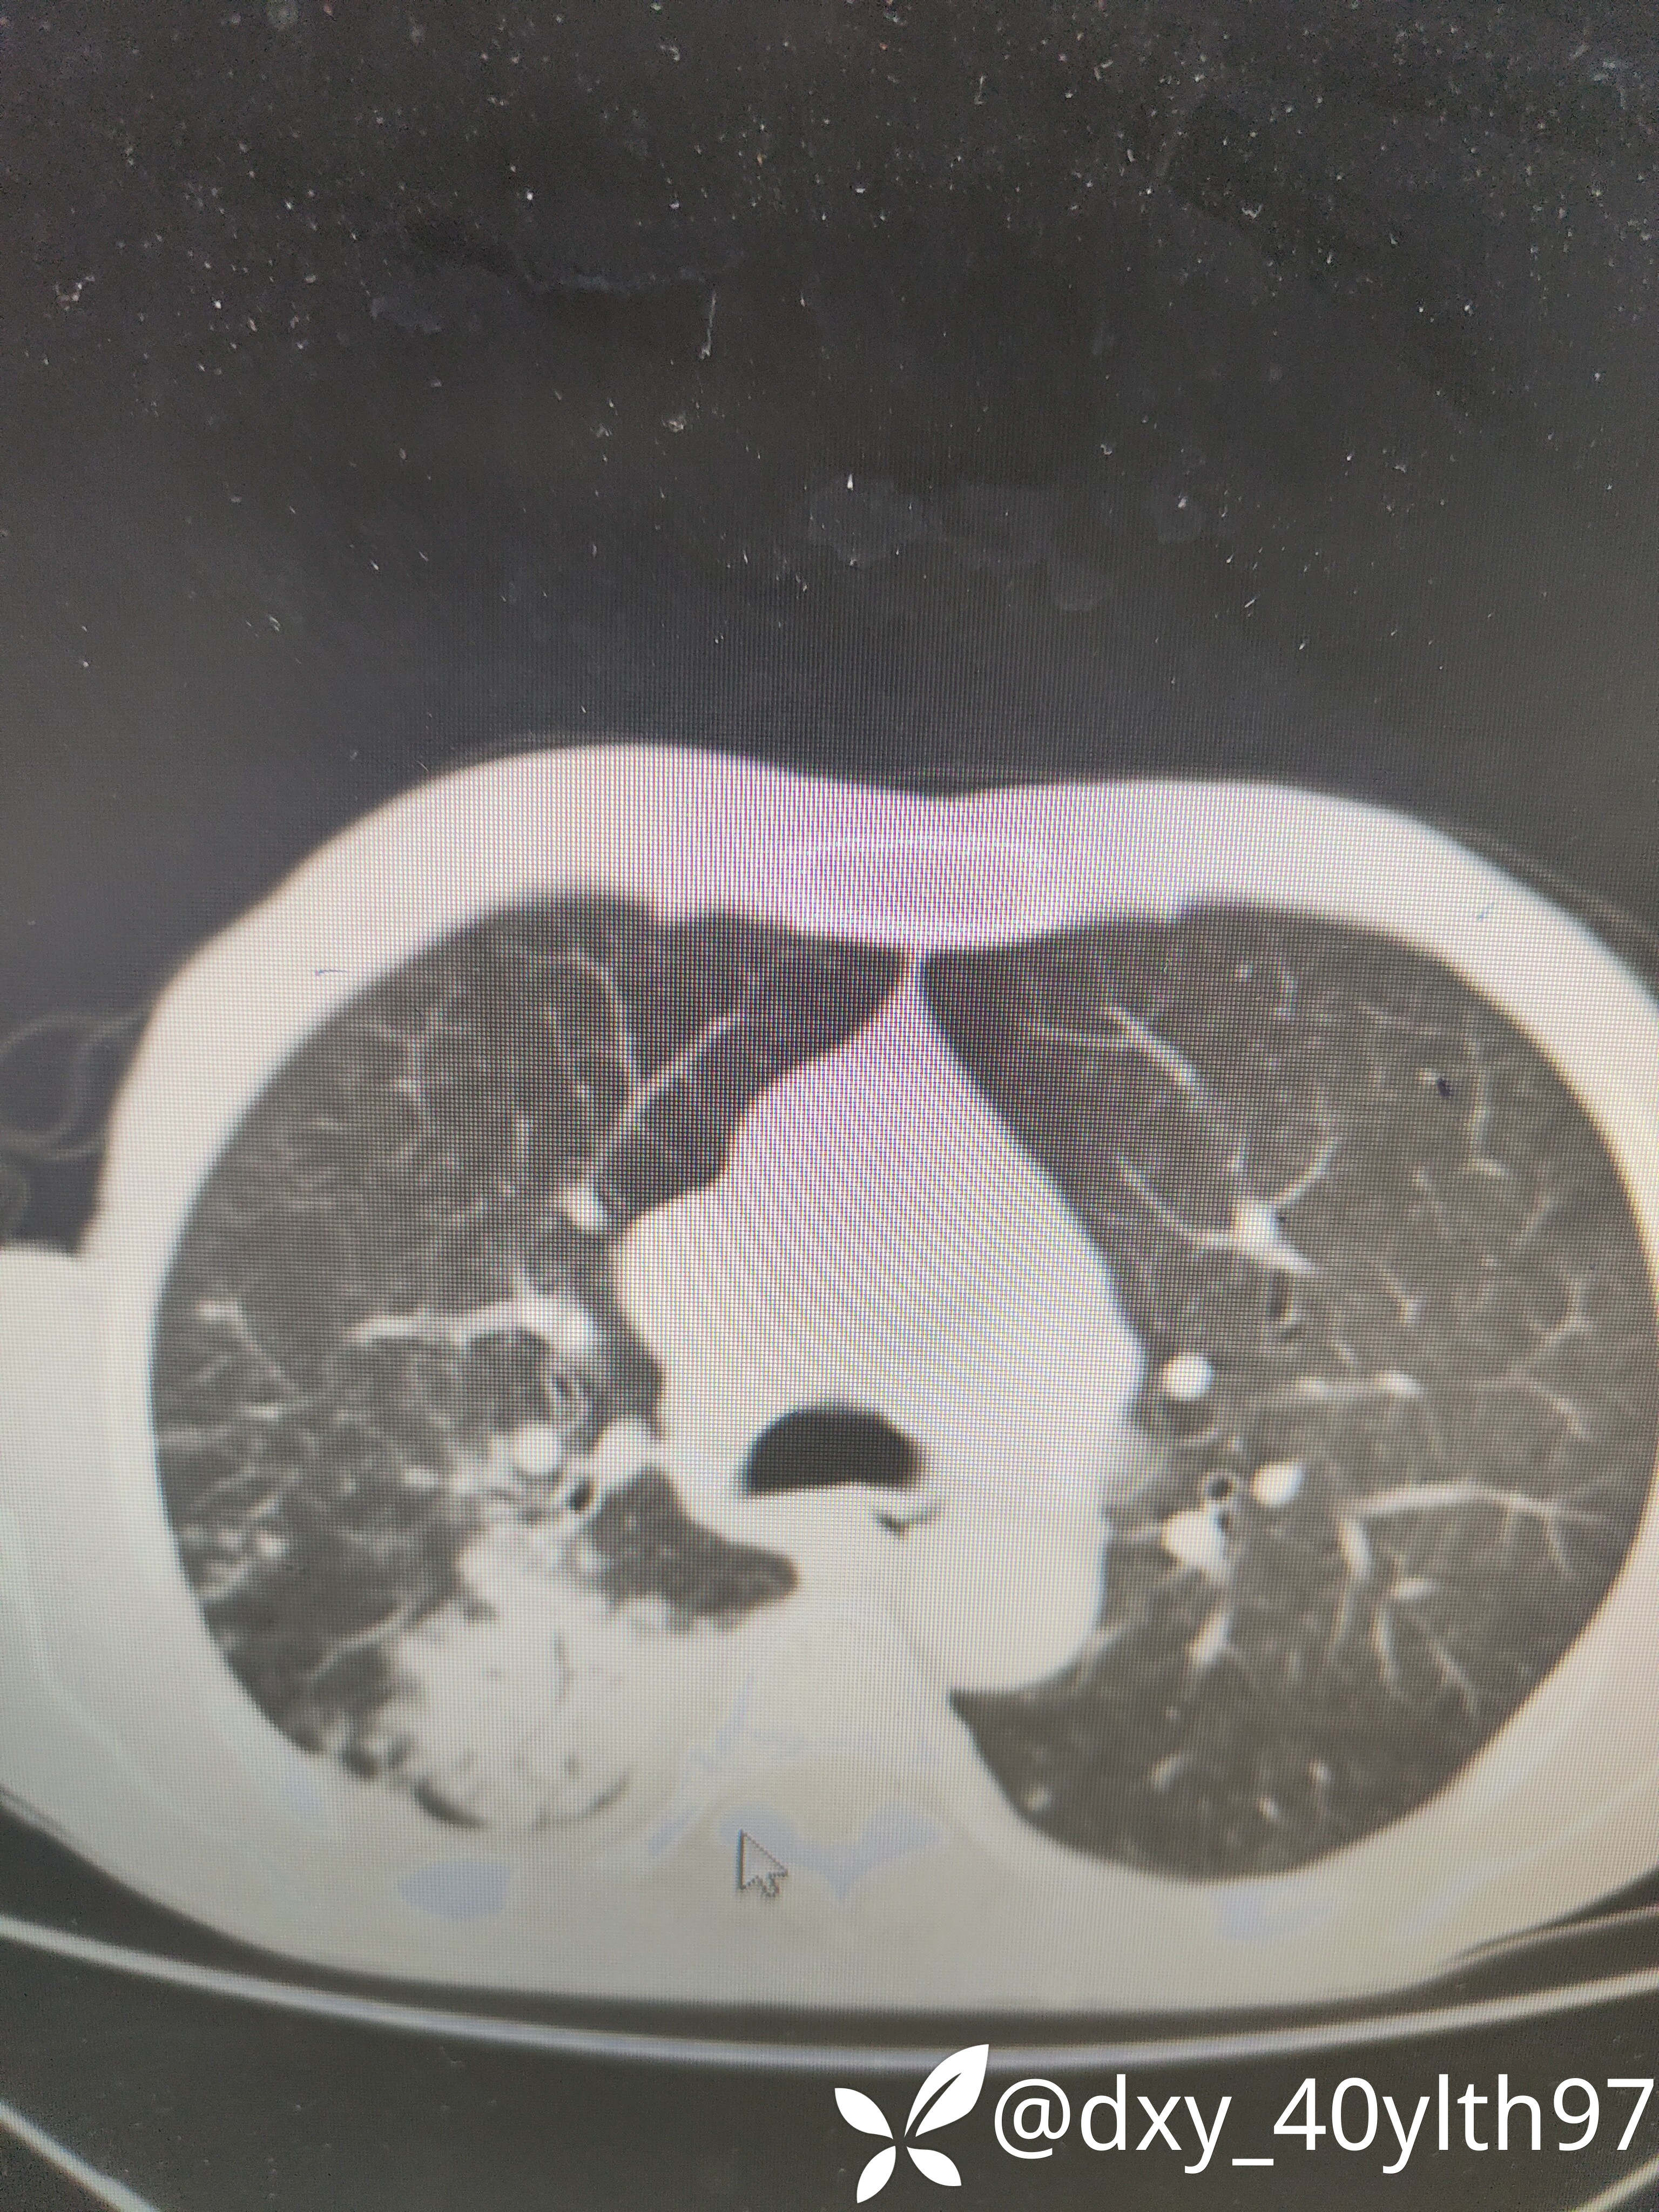

2023年8月肺部CT平扫影像结果提示:1.右肺上叶密度增高影较前显著增大,建议进一步检查;2.两肺多发斑片结节灶较前增多,部分增大。

肺部增强CT影像学提示:右肺内大片不规则影轻度强化,肿瘤可能。

肺穿刺活检病检提示:(右肺活检组织)慢性肉芽肿性伴坏死